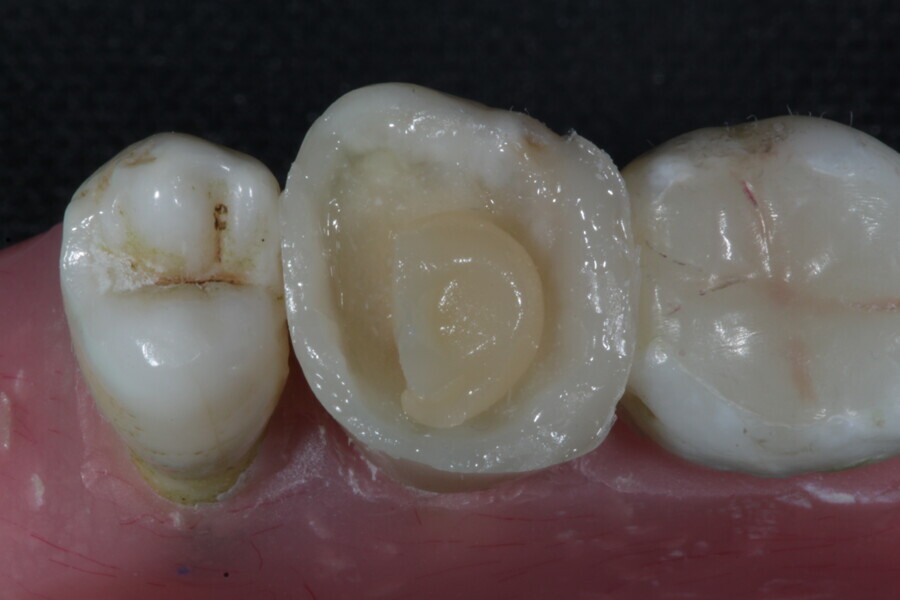

1. direct restoration using a fibre-reinforced flowable composite and membrane cube after endodontic treatment (Figs. 21–35); and

1. restoration reinforcement of a vital tooth with a fibre-reinforced flowable composite and membrane (Figs. 36–45).

Example 3—Restoration reinforcement of a vital tooth with a fibre-reinforced flowable composite and membrane.